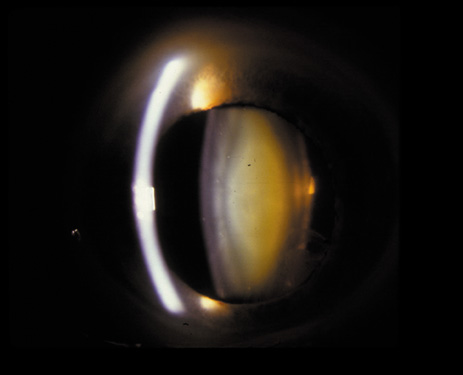

PSC may also result from irradiation or steroid ingestion, or it may be associated with diabetes, high myopia,37–41 retinal degeneration (e.g., retinitis pigmentosa),42,43 and gyrate atrophy.44,45 In some cases, the PSC eventually may be pushed to the cortex as new fibers are laid down and the offending agent is no longer present (Fig. 16A and B).

Fig. 16. A: Scheimpflug slit image of two types of PSCs (steroid-induced and gyrate atrophy-related) showing the positions of the opacities. B: Densitometry profiles showing the position of the gyrate atrophy-related PSC in comparison with the steroid-induced PSC. These suggest that the PSC migrates anteriorly as the newly laid down fibers push the PSC deeper into the cortex.45